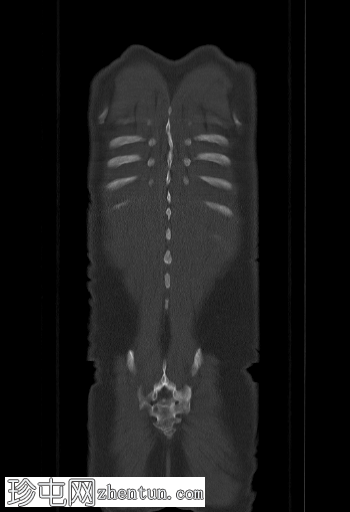

冠状位

SPECT-CT

冠状位融合

SPECT/CT

脊柱、肋骨、骨盆、颅骨、肩胛骨、胸骨、左侧肱骨和双侧股骨干可见多处放射性示踪剂摄取异常增高,与SPECT-CT扫描图像上显示的硬化病灶相对应。双肾未见放射性示踪剂活性。

骨骼内多处局灶性放射性示踪剂摄取增高,符合骨转移;肾脏内无放射性示踪剂活性,与超扫描结果一致。